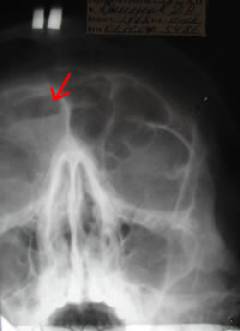

Как выглядит фронтит на снимке?

На рентгеновских снимках воспаленная лобная пазуха выглядит следующим образом: